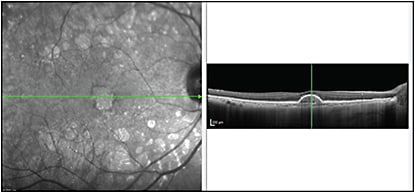

Pigment epithelial detachments (PED) can often appear optically empty on conventional SD-OCT images, whereas with EDI-OCT, the contents of the PED can be better visualized.9 Using EDI-OCT, Spaide et al were able to demonstrate the choroidal neovascularization within the PED as a hyper-reflective layer of tissue under the back surface of the RPE (Figure 2).10